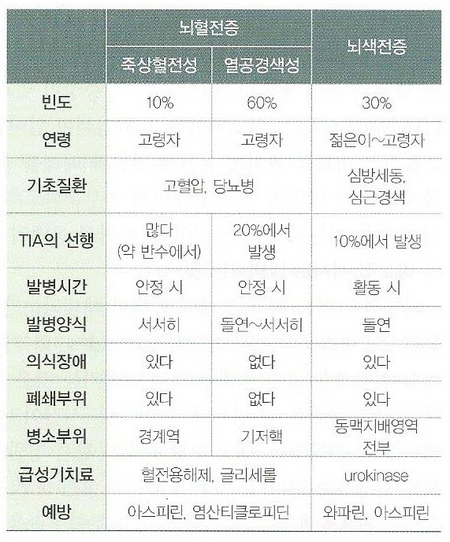

뇌경색, 뇌출혈, 일과성 뇌허혈 발작을 선행시키는 발병 시간 주로 안정시(뇌색전증은 활동시) 활동시 급성기 1시간~수일 직후~6시간 고혈압이 있거나 많이 있다, 두통, 구토 거의 없다, 많다.증상마비 > 의식장애 의식장애 > 마비뇌경색과 뇌출혈을 구별하는 것은 매우 중요하며 감별점은 위 표와 같습니다. 뇌출혈이 급하면 뇌경색은 상대적으로 완만합니다. 하지만 비교적 큰 뇌혈관이 막히거나 뇌색전으로 인한 뇌경색도 급격히 진행될 수 있습니다.

혈전은 비교적 천천히 동맥의 협착과 폐쇄를 일으킵니다. 그리고 어느 정도 두께의 동맥이 폐쇄되느냐에 따라 혈전성 뇌경색과 열공성 뇌경색으로 구분합니다. 전자는 비교적 굵은 동맥(전·중·후대뇌동맥)에 발생하고 후자는 관통동맥(교합혈관이 없는 동맥)에 생깁니다.

2) 색전 색전은 폐쇄 혈관 부위와 다른 곳에서 생긴 혈전이 흘러들어와 갑자기 혈류를 막는 것입니다. 대부분은 심장 내에서 생긴 혈전이 혈류를 타고 흘러 뇌동맥을 폐쇄합니다. 심판막증이나 심방세동의 좌심방벽, 심근경색의 수심실벽에서 발생하는 혈전 등이 뇌경색의 원인이 됩니다.뇌혈전(혈전성, 열공성)과 뇌색전의 차이는 아래 표와 같습니다.